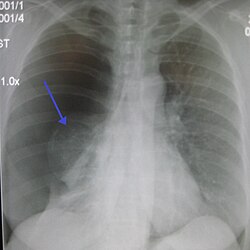

sağtərəfli spontan pnevmotoraks (şəkildə solda), ox işarəsilə büzüşmüş ağciyərin kənarı göstərilmişdir